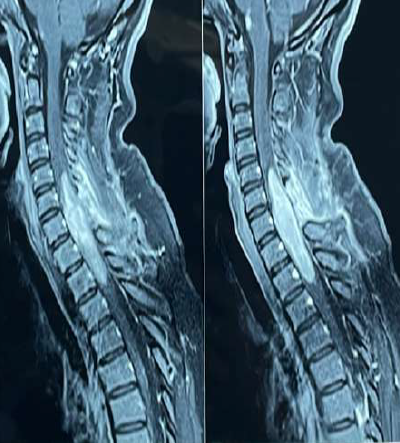

Presigmoid transpetrous approach (partial petrosectomy) combined with subtemporal transtentorial approach for petroclival meningioma

FERNANDO PALACIOS S., MANUEL LAZON A., EDUARDO ROMERO V., ROMMEL RODRIGUEZ B.